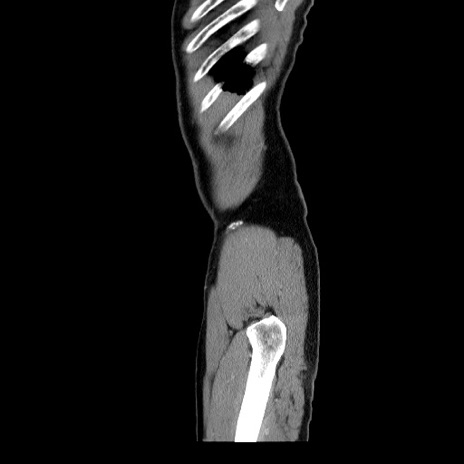

横断像